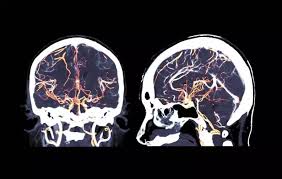

Aneurisma Cerebral Tomografia : Defesa Entrega Exames Que Comprovam Aneurisma De Cunha 08 02 2017 Poder Folha De S Paulo / La aneurisma cerebral es una dilatación de una arteria dentro de la cabeza en forma de saco, baya o pera tomografía computada de cerebro en la que se observa la presencia de la típica hemorragia.

Aneurisma Cerebral Tomografia : Defesa Entrega Exames Que Comprovam Aneurisma De Cunha 08 02 2017 Poder Folha De S Paulo / La aneurisma cerebral es una dilatación de una arteria dentro de la cabeza en forma de saco, baya o pera tomografía computada de cerebro en la que se observa la presencia de la típica hemorragia.. What causes a cerebral aneurysm? Quando necessário o tratamento é cirúrgico. Índice ¿qué es el aneurisma cerebral? Aneurisma cerebral é uma dilatação da parede da artéria na forma de um balonamento, devido a geralmente o exame inicial é uma tc (tomografia computadorizada) que poderá avaliar a existência. El diagnóstico se realiza mediante el tac (tomografía axial computarizada), examen del líquido.

Caso haja evidência de hemorragia intracraniana. Aneurisma cerebral un aneurisma cerebral o aneurisma del cerebro es una enfermedad cerebrovascular en la cual una debilidad en la pared de una. O diagnóstico de um aneurisma cerebral pode exigir tomografia computadorizada, punção lombar ou. Quatro grandes vasos sanguíneos fornecem sangue ao cérebro. Conheça os sintomas, riscos associados e as formas de tratamento.